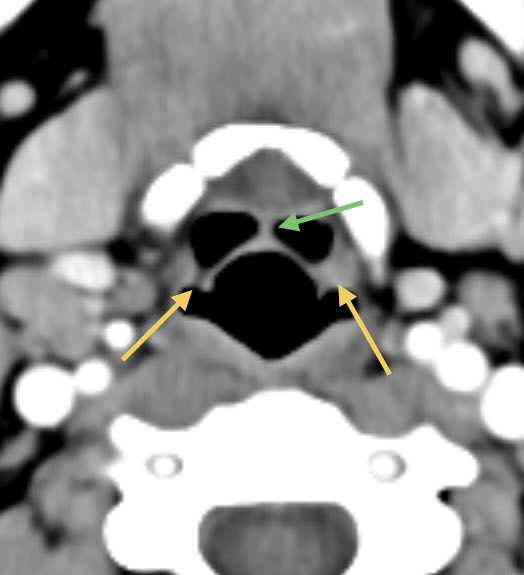

4️⃣Ganglioglioma

▶️Occurs in children and young adults

▶️Location: Temporal lobe (most common)

Imaging (variable and can look very similar to PXA):

▶️Classically presents as a cystic and solid mass in the temporal lobe in a child/young adult with seizures

▶️Presence of CALCIFICATIONS & LACK OF DURAL TAIL may help to differentiate from PXA ImageImageImage

Companion case of another ganglioglioma ImageImageImageImage